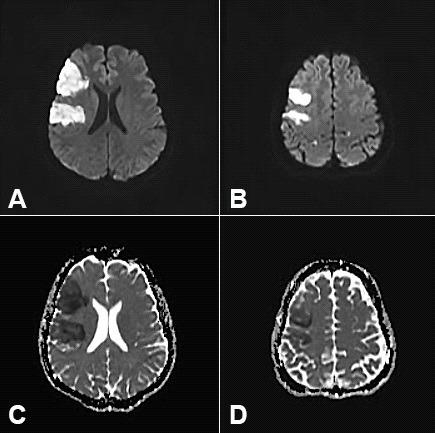

中枢神经系统(CNS)缺血性事件不仅是一种常见且具有破坏性的疾病,还伴有严重残疾和其他病症。此类事件的病因并不总是那么容易诊断,对于年轻人而言,应考虑多种可能性。我们报告一例年轻男性病例,其出现了两次中枢神经系统缺血发作,两次发作间隔1年,均发生在他行走并背着沉重背包的相同情况下。第二次事件最初表现为短暂性脑缺血发作,次日继之以中风。诊断检查显示舌骨大角在内颈动脉上方有压痕,损伤了中膜和内膜层。在动脉损伤部位发现了一个微血栓,这解释了栓塞事件至中枢神经系统的来源。患者接受了手术,手术包括切除舌骨后角、切除颈内动脉受损段,随后用大隐静脉进行颈动脉-颈动脉搭桥术。术后恢复顺利,5个月随访情况良好。我们提请注意这种不寻常的中风病因,并介绍文献中报道的其他病例。